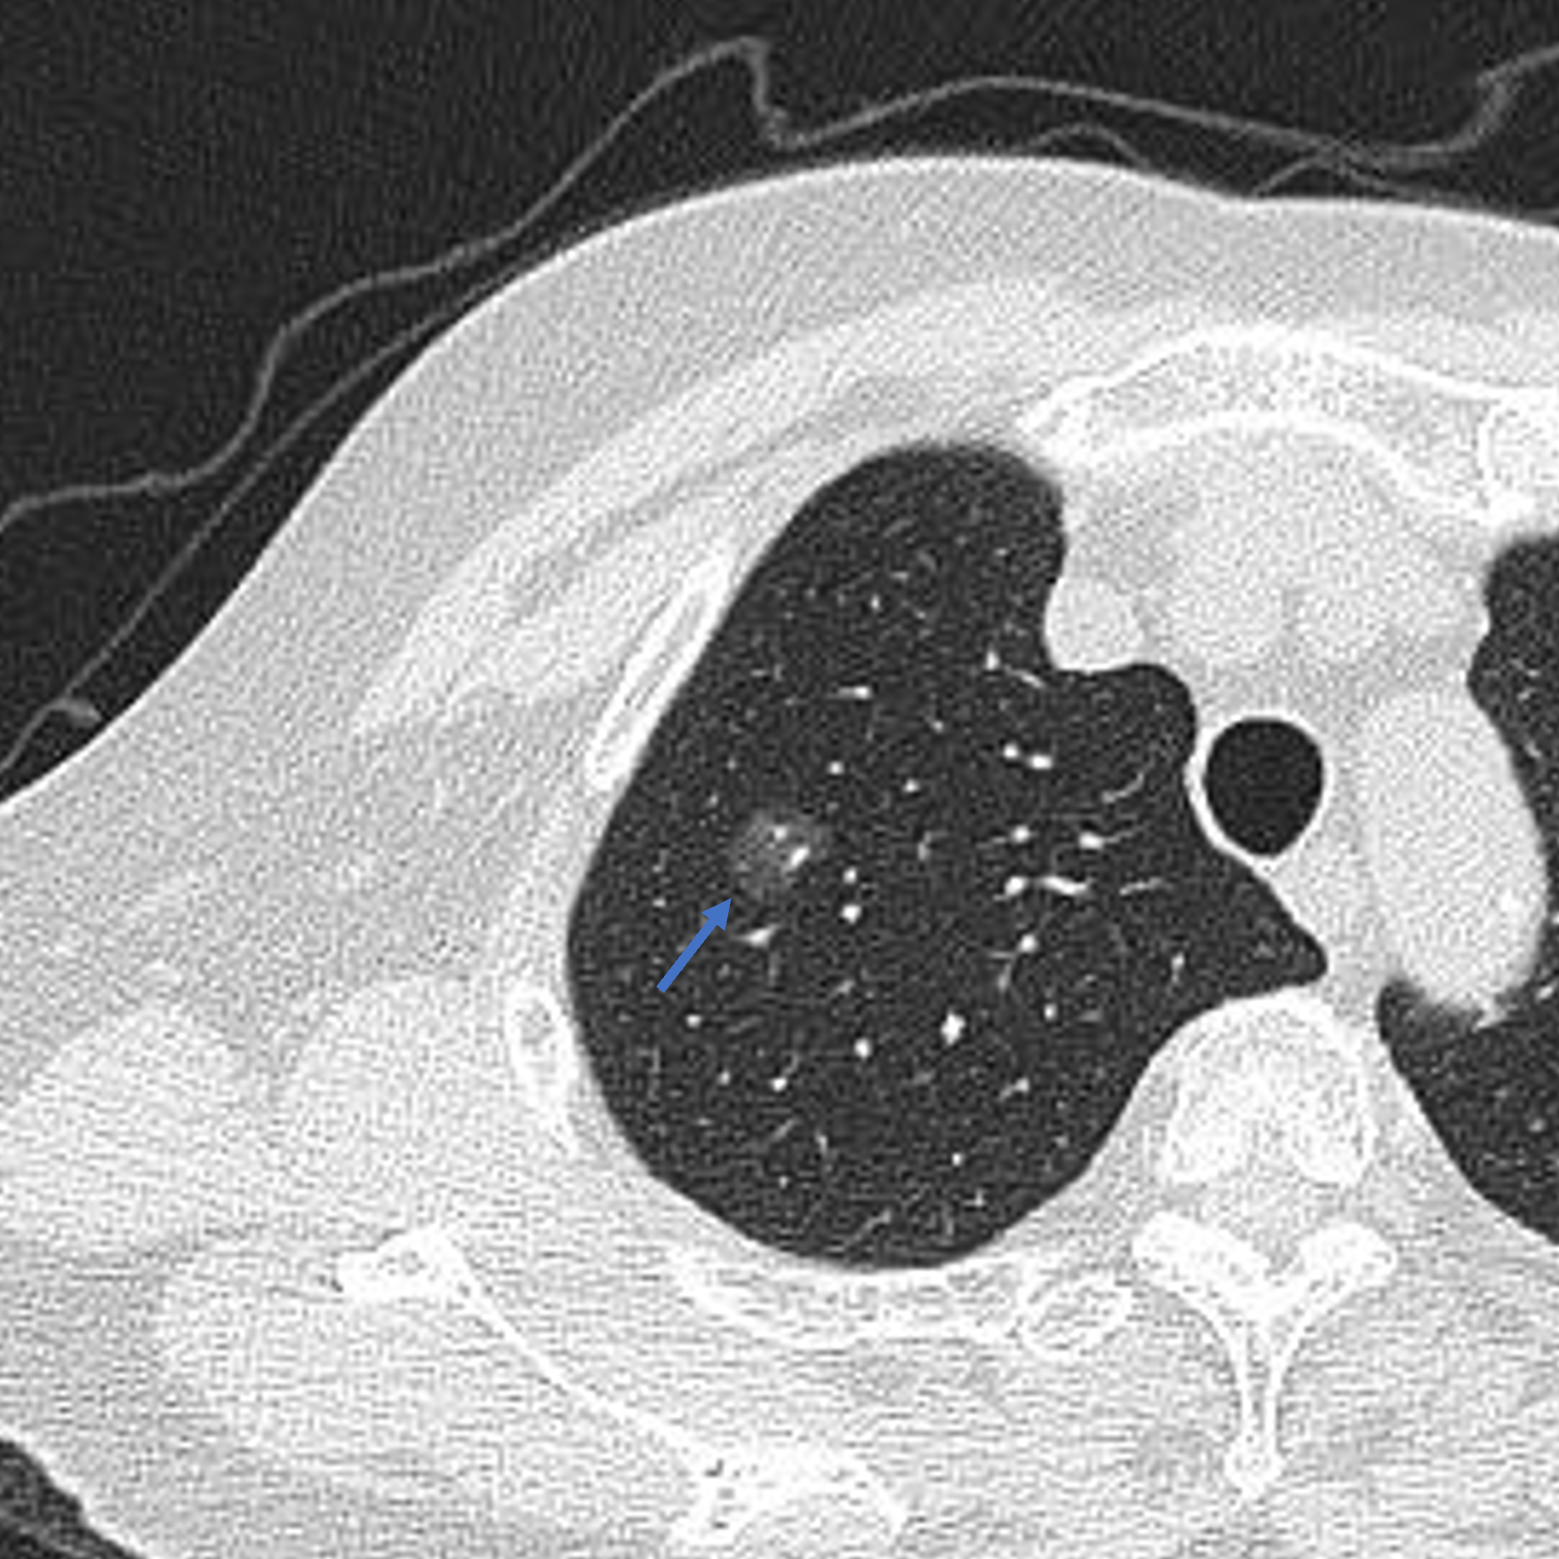

肺ct图示近脊柱处可见约18*14mm磨玻璃结节影